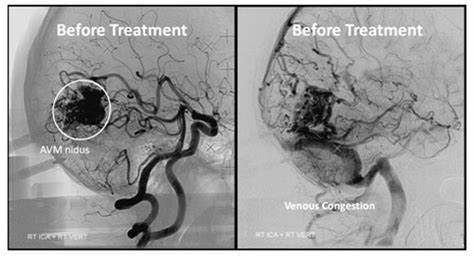

腦動靜脈畸形是由異常動脈和靜脈網(wǎng)絡(luò)組成的復(fù)雜結(jié)構(gòu),缺乏中間的毛細血管床,導(dǎo)致血液的高流量動靜脈分流。盡管已經(jīng)描述了家族性病例,但是動靜脈畸形是先天性的,并且大多數(shù)是偶發(fā)的。各種研究報告了與遺傳性出血性毛細血管擴張癥、斯特奇-韋伯病和威伯恩-梅森綜合征等疾病的聯(lián)系。動靜脈畸形常伴有顱內(nèi)出血,但也可出現(xiàn)癲癇發(fā)作、頭痛和局灶性神經(jīng)功能缺損。每年出血風(fēng)險通常為2%至4%,與5%至25%的死亡風(fēng)險和10%至50%的神經(jīng)殘疾風(fēng)險相關(guān)。Spetzler-Martin分級系統(tǒng)較初被認為是一種外科風(fēng)險評估工具,它為AVM大小、位置和靜脈引流模式分配分數(shù),通常用于描述臨床環(huán)境中的動靜脈畸形。

目前腦動靜脈畸形的治療方式包括顯微外科手術(shù)、血管內(nèi)栓塞和立體定向放射外科手術(shù)。雖然這些方法可以單獨使用,但通常需要聯(lián)合使用才能達到較佳治療效果。確定干預(yù)的類型或是否應(yīng)該干預(yù)可能很困難。較終,應(yīng)進行風(fēng)險效益分析,根據(jù)與擬議干預(yù)措施相關(guān)的風(fēng)險考慮AVM的自然歷史。面對較近的報告表明,醫(yī)療管理可能優(yōu)于介入治療未破裂的動靜脈畸形,至少在短期內(nèi),這種分析變得更加重要。組建一支在動靜脈畸形的醫(yī)學(xué)、外科、血管內(nèi)和放射治療方面具有知識的多學(xué)科團隊,對于妥善管理這種復(fù)雜病變的患者至關(guān)重要。

血管內(nèi)的知識應(yīng)該在全部動靜脈畸形的多學(xué)科治療中占有重要地位。除了少數(shù)的例外,全部的動靜脈畸形都應(yīng)該用導(dǎo)管腦血管造影來描述,即使保守治療是可能的。對動脈-靜脈血流動力學(xué)、供血血管和引流靜脈的數(shù)量和位置以及相關(guān)動脈瘤或靜脈流出道梗阻的存在的評估對于適當(dāng)?shù)臎Q策至關(guān)重要。如果選擇血管內(nèi)介入治療,可能的治療策略包括手術(shù)前栓塞、放射手術(shù)前栓塞、治療性栓塞或姑息性栓塞。

在開始對大腦AVM進行治療之前,患者了解自然史以及與治療相關(guān)的風(fēng)險和益處是至關(guān)重要的。這些復(fù)雜和危險病變的順利、明確治療需要有經(jīng)驗的多學(xué)科團隊的協(xié)調(diào)。與一個未經(jīng)治療的大腦AVM生活在一起所帶來的焦慮和不確定性對患者和他們的家人來說都是一個而普遍的負擔(dān)。事實上,對于許多希望長期根除AVM病的患者來說,一個實質(zhì)性的前期手術(shù)風(fēng)險可能是值得的。栓塞是腦動靜脈畸形綜合治療的重要組成部分。顯然,如果不明智地使用這種方式,許多AVM是無法順利治愈的。